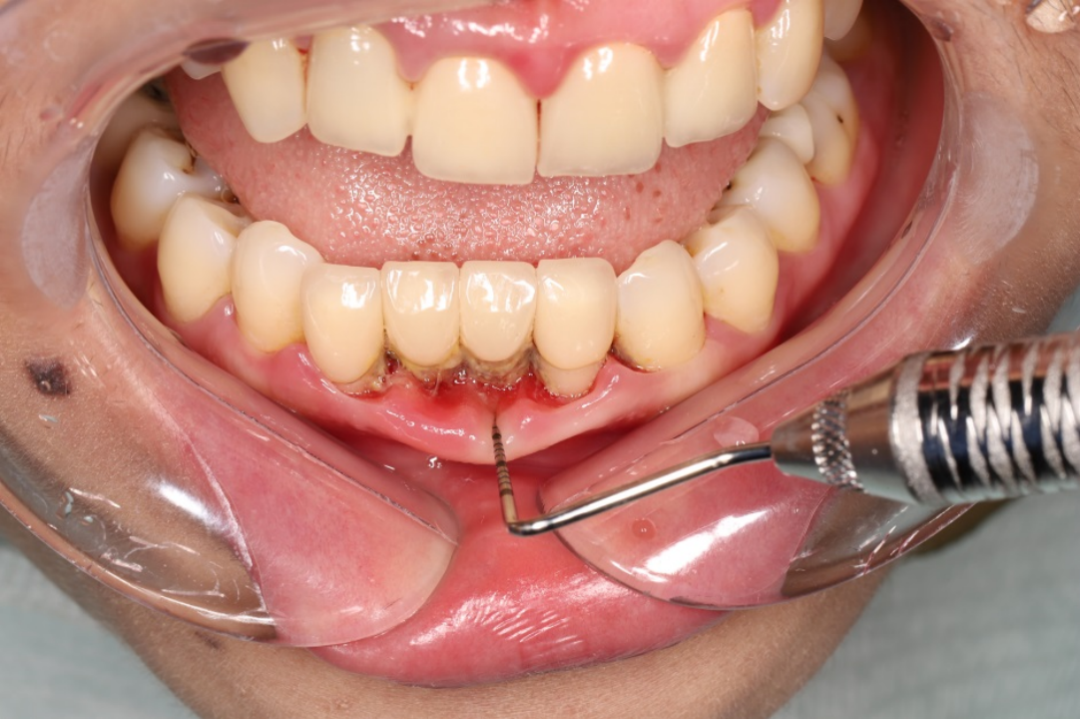

▲第一次洗牙后,牙齿“重见天日”

洗完牙后,全口牙结石被清除,牙周炎给牙齿造成的破坏——牙龈退缩、牙周袋形成、牙槽骨吸收等,完全呈现在谢先生面前。